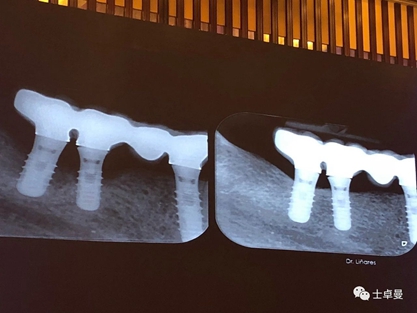

種植體周圍炎是影響牙種植遠(yuǎn)期效果導(dǎo)致種植失敗的主要原因之一。和天然牙一樣,如果口腔衛(wèi)生不良,菌斑滯留,那么細(xì)菌微生物就會(huì)對種植體周圍的軟組織不斷刺激,使機(jī)體產(chǎn)生炎癥反應(yīng),表現(xiàn)為黏膜的紅腫、探診出血甚至溢膿。也可通過X片來評估種植體周圍的骨量情況。

4、種植體周圍炎的治療

接下來Dr. Laurence Adriaens介紹了種植體周圍炎的治療,即非手術(shù)方式治療和手術(shù)方式治療。非手術(shù)方式治療提倡對患者進(jìn)行有效的口腔衛(wèi)生指導(dǎo),患者必須掌握有效的菌斑控制方法,以保持良好的口腔衛(wèi)生,還可以選用種植體專用的牙線清潔義齒鄰面及其周圍軟組織。同時(shí)應(yīng)養(yǎng)成每半年到一年定期復(fù)查,進(jìn)行專業(yè)清潔的習(xí)慣。

手術(shù)方式治療則需通過翻瓣清潔種植體及修復(fù)體上菌斑牙石,推薦在此過程中使用士卓曼鈦刷,因?yàn)樵撯佀⒉粫?huì)損傷種植體表面細(xì)微結(jié)構(gòu)。之后進(jìn)行植骨蓋膜來促進(jìn)種植體周圍吸收部分的骨的重建。